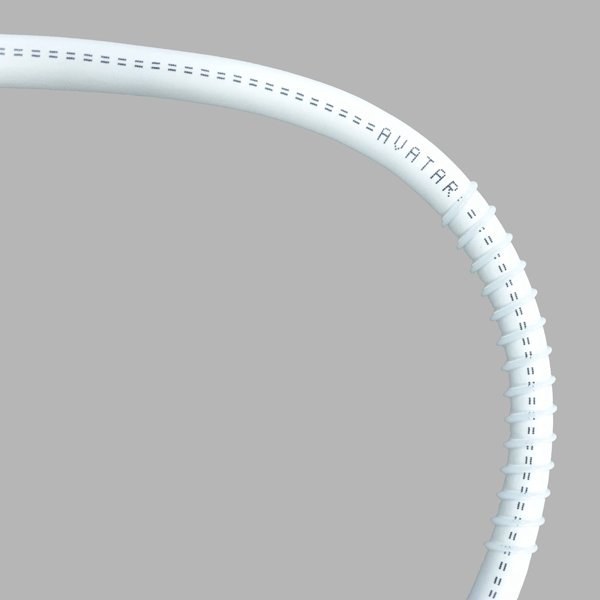

Arterio-Venous Grafts – Center Helix (non-removable)

| 5 | 45cm | 5mm | PVGCH0545 |

| 6 | 45cm | 6mm | PVGCH0645 |

Arterio-Venous Grafts – End Helix (non-removable)

| 7 | 45cm | 5mm | PVGEH0545 |

| 8 | 45cm | 6mm | PVGEH0645 |

Arterio-Venous Grafts – Step-Tapered Center Helix (non-removable)

| 11 | 45cm | 4-6mm | PVGSC4645 |

| 12 | 45cm | 4-7mm | PVGSC4745 |

AVATAR® PTFE Vascular Grafts are made entirely from PTFE. The AVATAR® graft does not have an external wrap but instead has an open pore structure averaging 20 microns internodal distance, encouraging tissue ingrowth and making it soft and easy to suture. Helix grafts incorporate an external PTFE spiral support for use in applications where kink or crush resistance is required. Tapered and step tapered grafts can allow for better management of blood flow. All AVATAR® PTFE Vascular Grafts come sterile in dual barrier tray-within-tray packaging.